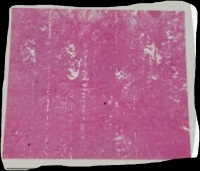

男,21岁,额头部长一包块半年余,不痛不痒,病理描述:表皮角化过度,表皮突延长增宽,真皮可见增生的成纤维细胞及胶原纤维,呈交织状或漩涡状排列,周围无包膜,周边部位胶原束增粗。